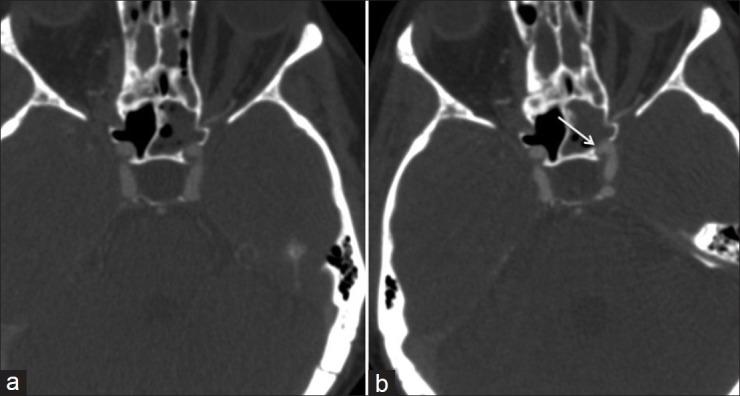

In this study we describe endovascular parent vessel wall-remodeling/endoluminal reconstruction and traumatic pseudoaneurysm thrombosis through the use of the Pipeline stent and review recent reports concerning indications, safety, and efficacy for alternative pathology.

Although currently not routinely employed in the treatment of traumatic pseudoaneurysms, the Pipeline stent may represent a safe and effective treatment alternative achieving complete endoluminal reconstruction of the damaged vessel wall.